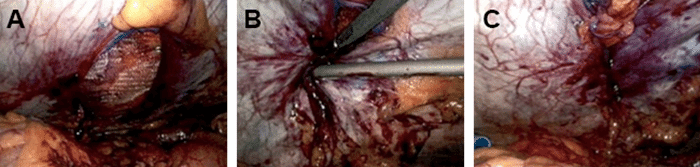

Figure 3. Hernia Operation. Published with Permission

A) Mesh was placed and then expanded within posterior rectus sheath; B) The mesh was then secured with titanium tacker; C) Completed RUQ hernia repair with complete peritoneal covering of the mesh

By applying traction and sharp dissection, the epigastric midline hernias were easily reduced. Chronically incarcerated omentum and a portion of the proximal transverse colon were noted within the larger RUQ incisional hernia. The peritoneal adhesions around the perimeter of the hernia sac were sharply divided, facilitating reduction of both the omentum and the colon. The reduced colon and omentum were inspected and found to be without any injury or ischemic areas. The posterior rectus sheath defect measured about 5 cm × 7.5 cm. The space noted above the defect was approximately a 15 cm wide diameter circle. No attempt was made to remove the hernia sac.

A 15 cm × 15 cm square of lightweight polypropylene mesh (ProLite™, Atrium Medical Corporation) was trimmed to form a 15 cm × 15 cm circular mesh. The mesh was rolled up and inserted into the abdomen through the 12 mm camera port. Upon insertion, the mesh was unrolled and placed into the defect between the right posterior rectus sheath and the overlying rectus abdominis muscle. It was expanded and secured in this location by tacking the edges to the overlying rectus muscle in a few locations. Overlapping closure of the peritoneum and complete coverage of the mesh was achieved in a “vest over pants” fashion, facilitated by decreasing the insufflation pressure to 5 mmHg.